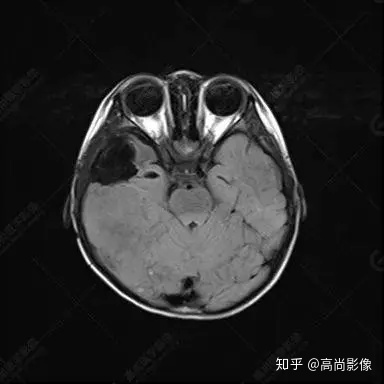

右側(cè)顳葉腫瘤切除術(shù)后(具體不詳):右側(cè)顳部骨質(zhì)不連續(xù)呈術(shù)后改變,右側(cè)顳葉術(shù)區(qū)見片狀長T1長T2信號(hào)影,F(xiàn)LAIR呈低信號(hào);術(shù)區(qū)后方右側(cè)顳枕葉見一巨大占位性病變影,邊界欠清,大小約6.2×5.8×4.3cm(前后×左右×上下),信號(hào)不均勻,T1WI呈等稍低信號(hào)間雜少許高信號(hào),T2WI呈高稍低混雜信號(hào),DWI示部分病灶彌散受限,相應(yīng)ADC圖減低,磁敏感序列見部分呈極低信號(hào),增強(qiáng)掃描可見明顯不均勻強(qiáng)化,鄰近硬腦膜及小腦幕增厚并明顯強(qiáng)化;另延髓右前方及右側(cè)橋小腦角區(qū)見一不規(guī)則形異常信號(hào)影,大小約3.2×1.3×3.7cm(左右×前后×上下),呈長T1稍長T2信號(hào),F(xiàn)LAIR呈等信號(hào),DWI未見受限,增強(qiáng)后明顯均勻強(qiáng)化,鄰近腦膜明顯強(qiáng)化。鄰近腦實(shí)質(zhì)及右側(cè)顳角明顯受壓;左側(cè)大腦半球未見局灶性信號(hào)異常,中線結(jié)構(gòu)稍左移。

右側(cè)顳葉腫瘤切除術(shù)后:現(xiàn)術(shù)區(qū)后方右側(cè)顳枕葉及延髓右前方占位,右側(cè)顳枕部硬腦膜及小腦幕明顯強(qiáng)化,結(jié)合既往影像資料,考慮為胚胎源性惡性腫瘤,如非典型畸胎樣/橫紋肌樣瘤(AT/RT)或原始神經(jīng)外胚層腫瘤(PNET)。

非典型畸胎樣/橫紋肌樣瘤(AT/RT) 是一種高度惡性中樞神經(jīng)系統(tǒng)腫瘤,臨床罕見,臨床表現(xiàn)無特異性,好發(fā)于 5 歲以下兒童,尤以 3 歲以下多見,在兒童原發(fā)性中樞神經(jīng)系統(tǒng)(CNS)腫瘤中占 1%~3%。該腫瘤體積一般較大,幕上大于幕下,有明顯的占位效應(yīng)。該腫瘤成分復(fù)雜,囊變、出血、壞死常見。因此 AT/RT信號(hào)混雜,囊性部分呈 T1WI低、T2WI高信號(hào),增強(qiáng)后不強(qiáng)化;若瘤體出血,囊內(nèi)可見T1WI稍高信號(hào)、T2WI低信號(hào),實(shí)性部分在 T1WI上呈混雜等、低信號(hào),在T2WI 及 T2-FLAIR上呈混雜等高信號(hào),增強(qiáng)掃描后大部分呈環(huán)形條帶樣明顯強(qiáng)化,中心壞死區(qū)不強(qiáng)化。另外,該腫瘤實(shí)性成分在DWI上呈高信號(hào),說明腫瘤細(xì)胞核密集,水分子擴(kuò)散明顯受限,提示該腫瘤惡性程度高,容易復(fù)發(fā)及轉(zhuǎn)移。